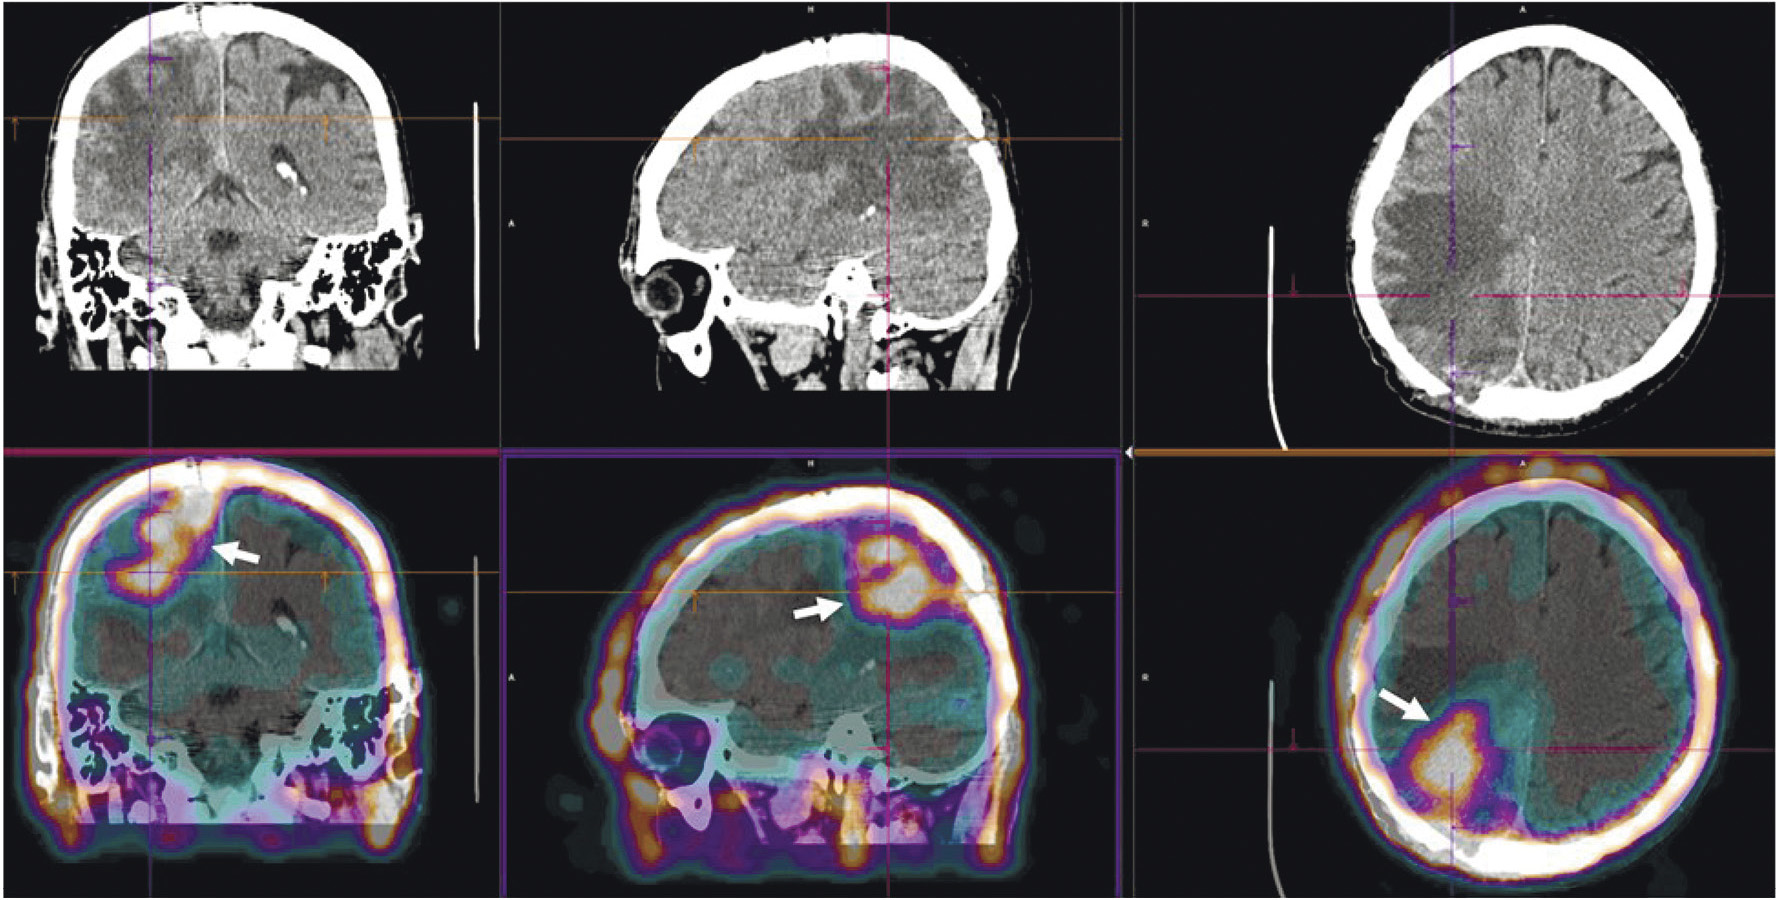

Радиофармпрепарат 99mTc-1-Тио-D-глюкоза и набор для его приготовления разработаны в НИИ онкологии Томского НИМЦ и ТПУ (“Тиоскан, 99mТс”, Россия). Неповреждённый гематоэнцефалический барьер непроницаем для данного препарата, поэтому 99mTc-1-Тио-D-глюкоза хорошо показала себя в диагностике опухолей головного мозга (рис. 7) [43]. Кроме того, ОФЭКТ/КТ с 99mTc-1-Тио-D-глюкозой рекомендована для стадирования и прогноза результатов лечения лимфопролиферативных заболеваний (рис. 8) [44, 45].

Рис. 7. ОФЭКТ/КТ с 99mTc-1-Тио-D-глюкозой пациента с рецидивом глиобластомы. Стрелками обозначено накопление РФЛП в опухоли

Рис. 8. ОФЭКТ/КТ с 99mTc-1-Тио-D-глюкозой пациентки с лимфомой Ходжкина. Стрелками обозначено накопление РФЛП в лимфатических узлах правой аксиллярной области